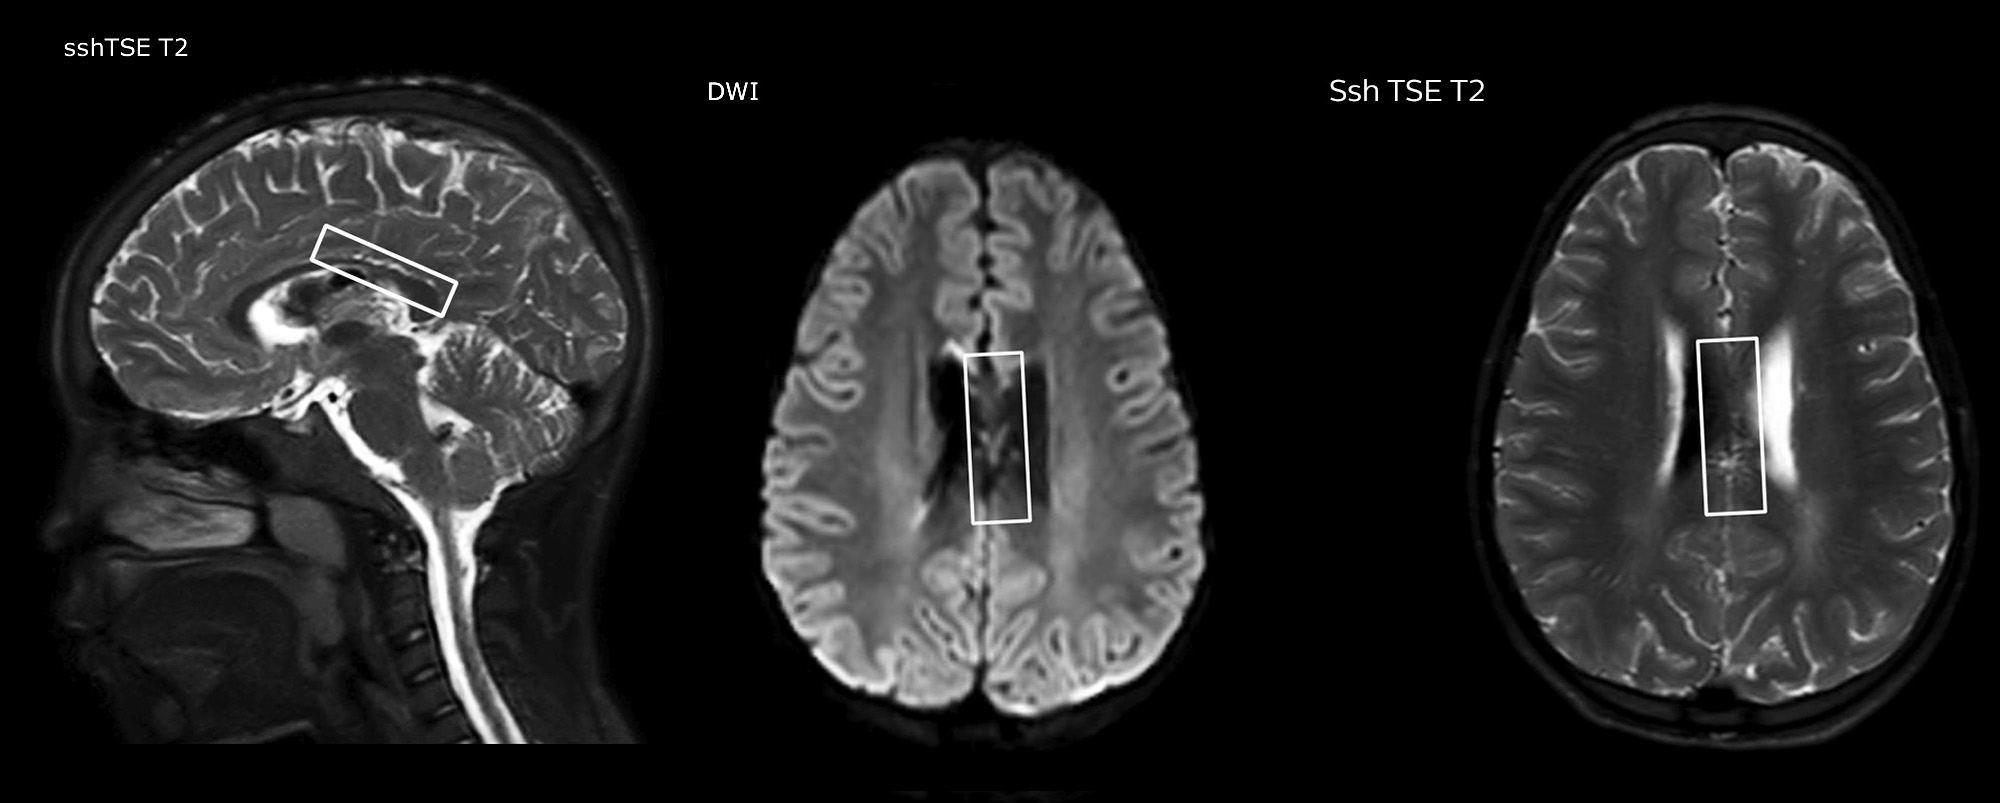

The value of susceptibility weighted imaging in visualizing brain injury is well documented. The Philips multi-echo SWIp technique provides fast susceptibility weighted imaging with enhanced susceptibility contrast and high resolution.

“Pediatric imaging is not without its challenges,” Dr. Miller says. “Since our patients are often very small, we need very high-resolution imaging. In cases of brain injury, we need to obtain information quickly so the treating clinicians can make decisions on care. We rely on high resolution and robust imaging capabilities, and SWIp provides that.”

“SWIp helps us identify blood or blood products, calcification, and diseases that affect the vascular system,” says Dr. Miller. “In children with traumatic brain injuries, it highlights areas that are injured, better than some of the previous techniques that we were using. These children often have micro-injuries that cause small amounts of blood or tissue damage. Adding SWIp helps us to better characterize the extent and nature of the injury. Having characterized an injury to the extent of what’s possible supports our diagnostic confidence.”

“I would definitely recommend other users to implement SWIp. We initially added the SWIp sequence following a lot of support for its utility in the literature. Then we directly compared SWIp to the 2D gradient echo sequences that we were using. After a good amount of clinical experience in seeing its benefits, we were confident to replace the old sequences with SWIp. It gives us a better assessment of the physiological processes of the brain that were less apparent on our previous imaging sequences,” says Dr. Miller. “SWIp is now a routine sequence for imaging traumatic brain injury patients at PCH, and it’s episodically added for patients who have intracranial vascular abnormalities.”

“I believe SWIp is rapidly becoming the standard in imaging traumatic brain injury, because of its high sensitivity to venous blood products. SWIp may even help attract patients; our neurosurgeons often ask to have the patients imaged on our scanners with highly sensitive techniques like SWIp. There’s also a growing application of SWI sequences in other vascular abnormalities because of the possibilities around physiological assessment of the brain than just a standard structural imaging.”